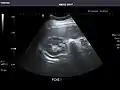

Pancreas